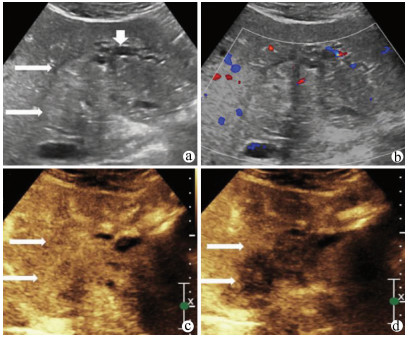

Guideline for ultrasonic diagnosis of liver diseases

Chinese Society of Ultrasound in Medicine, Oncology Intervention Committee of Chinese Research Hospital Society, National Health Commission Capacity Building and Continuing Education Expert Committee on Ultrasonic Diagnosis

2021, 37(8): 1770-1785. DOI: 10.3969/j.issn.1001-5256.2021.08.007

Abstract(3025) HTML (6526) PDF (9311KB)(794)

Abstract:

Ultrasound is a non-invasive, real-time, inexpensive, radiation-free and easily repeatable method, usually used for liver imaging. In recent years, new ultrasound examination techniques for liver diseases such as contrast-enhanced ultrasound and elastography have been rapidly developed, which can effectively identify intrahepatic space-occupying lesions, assess the degree of liver fibrosis and portal hypertension, and monitor the effects of treatment. Therefore, these technologies play an important diagnostic role in clinical liver diseases and have therapeutic interventional value. This guideline classifies the instrument set-up, patient preparation, and physician examination methods through multimodal ultrasound examinations (gray-scale ultrasound, color Doppler ultrasound, contrast-enhanced ultrasound, elastic ultrasound) for liver diseases. In addition, liver diseases multimodal ultrasound technology diagnostic criteria for diffuse hepatic lesions (inflammatory lesions, fibrosis, and sclerosis), multiple space-occupying lesions, and interventional procedures have been defined and standardized. Concurrently, we also recommend the ultrasound monitoring time interval and diagnostic report writing standard for liver diseases.